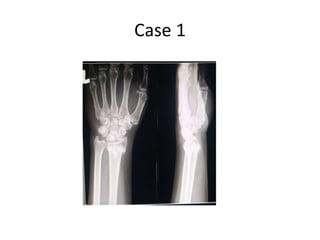

Case 1